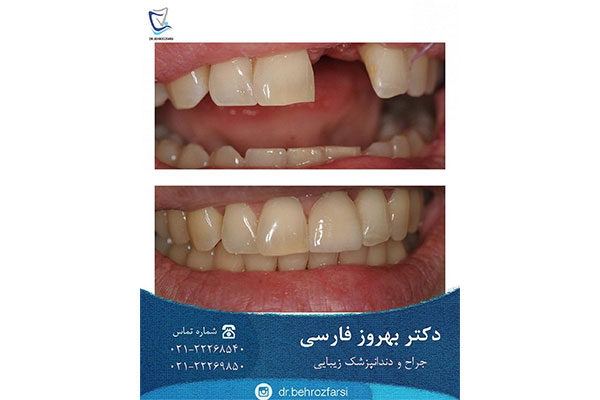

دندانپزشکی دکتر بهروز فارسی

- خدمات ایمپلنت دندان:

- مرکز تخصصی زیبایی و ایمپلنت های دندانی

- طرح لبخند

- ترمیم های زیبایی دندان

آدرس: خیابان شریعتی، ابتدای خیابان ظفر، نبش کوچه صبر، پلاک ۱، واحد ۱

تلفن: 22269850